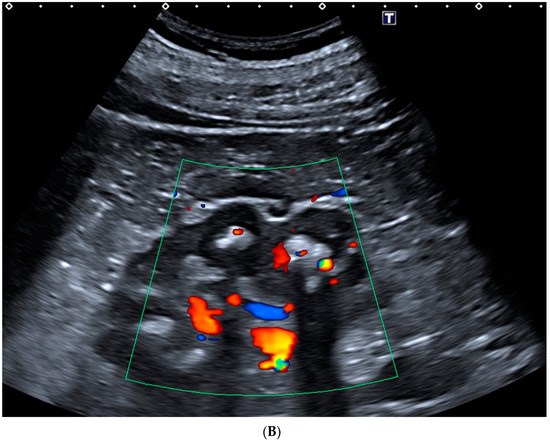

- Rahmouni, A.; Bargoin, R.; Herment, A.; Bargoin, N.; Vasile, N. Color Doppler twinkling artifact in hyperechoic regions. Radiology 1996, 199, 269–271. [Google Scholar] [CrossRef] [PubMed]

- Bardin, T.; Tran, K.M.; Nguyen, Q.D.; Sarfati, M.; Richette, P.; Vo, N.T.; Bousson, V.; Correas, J.-M. Renal medulla in severe gout: Typical findings on ultrasonography and dual-energy CT study in two patients. Ann. Rheum. Dis. 2018, 78, 433–434. [Google Scholar] [CrossRef]